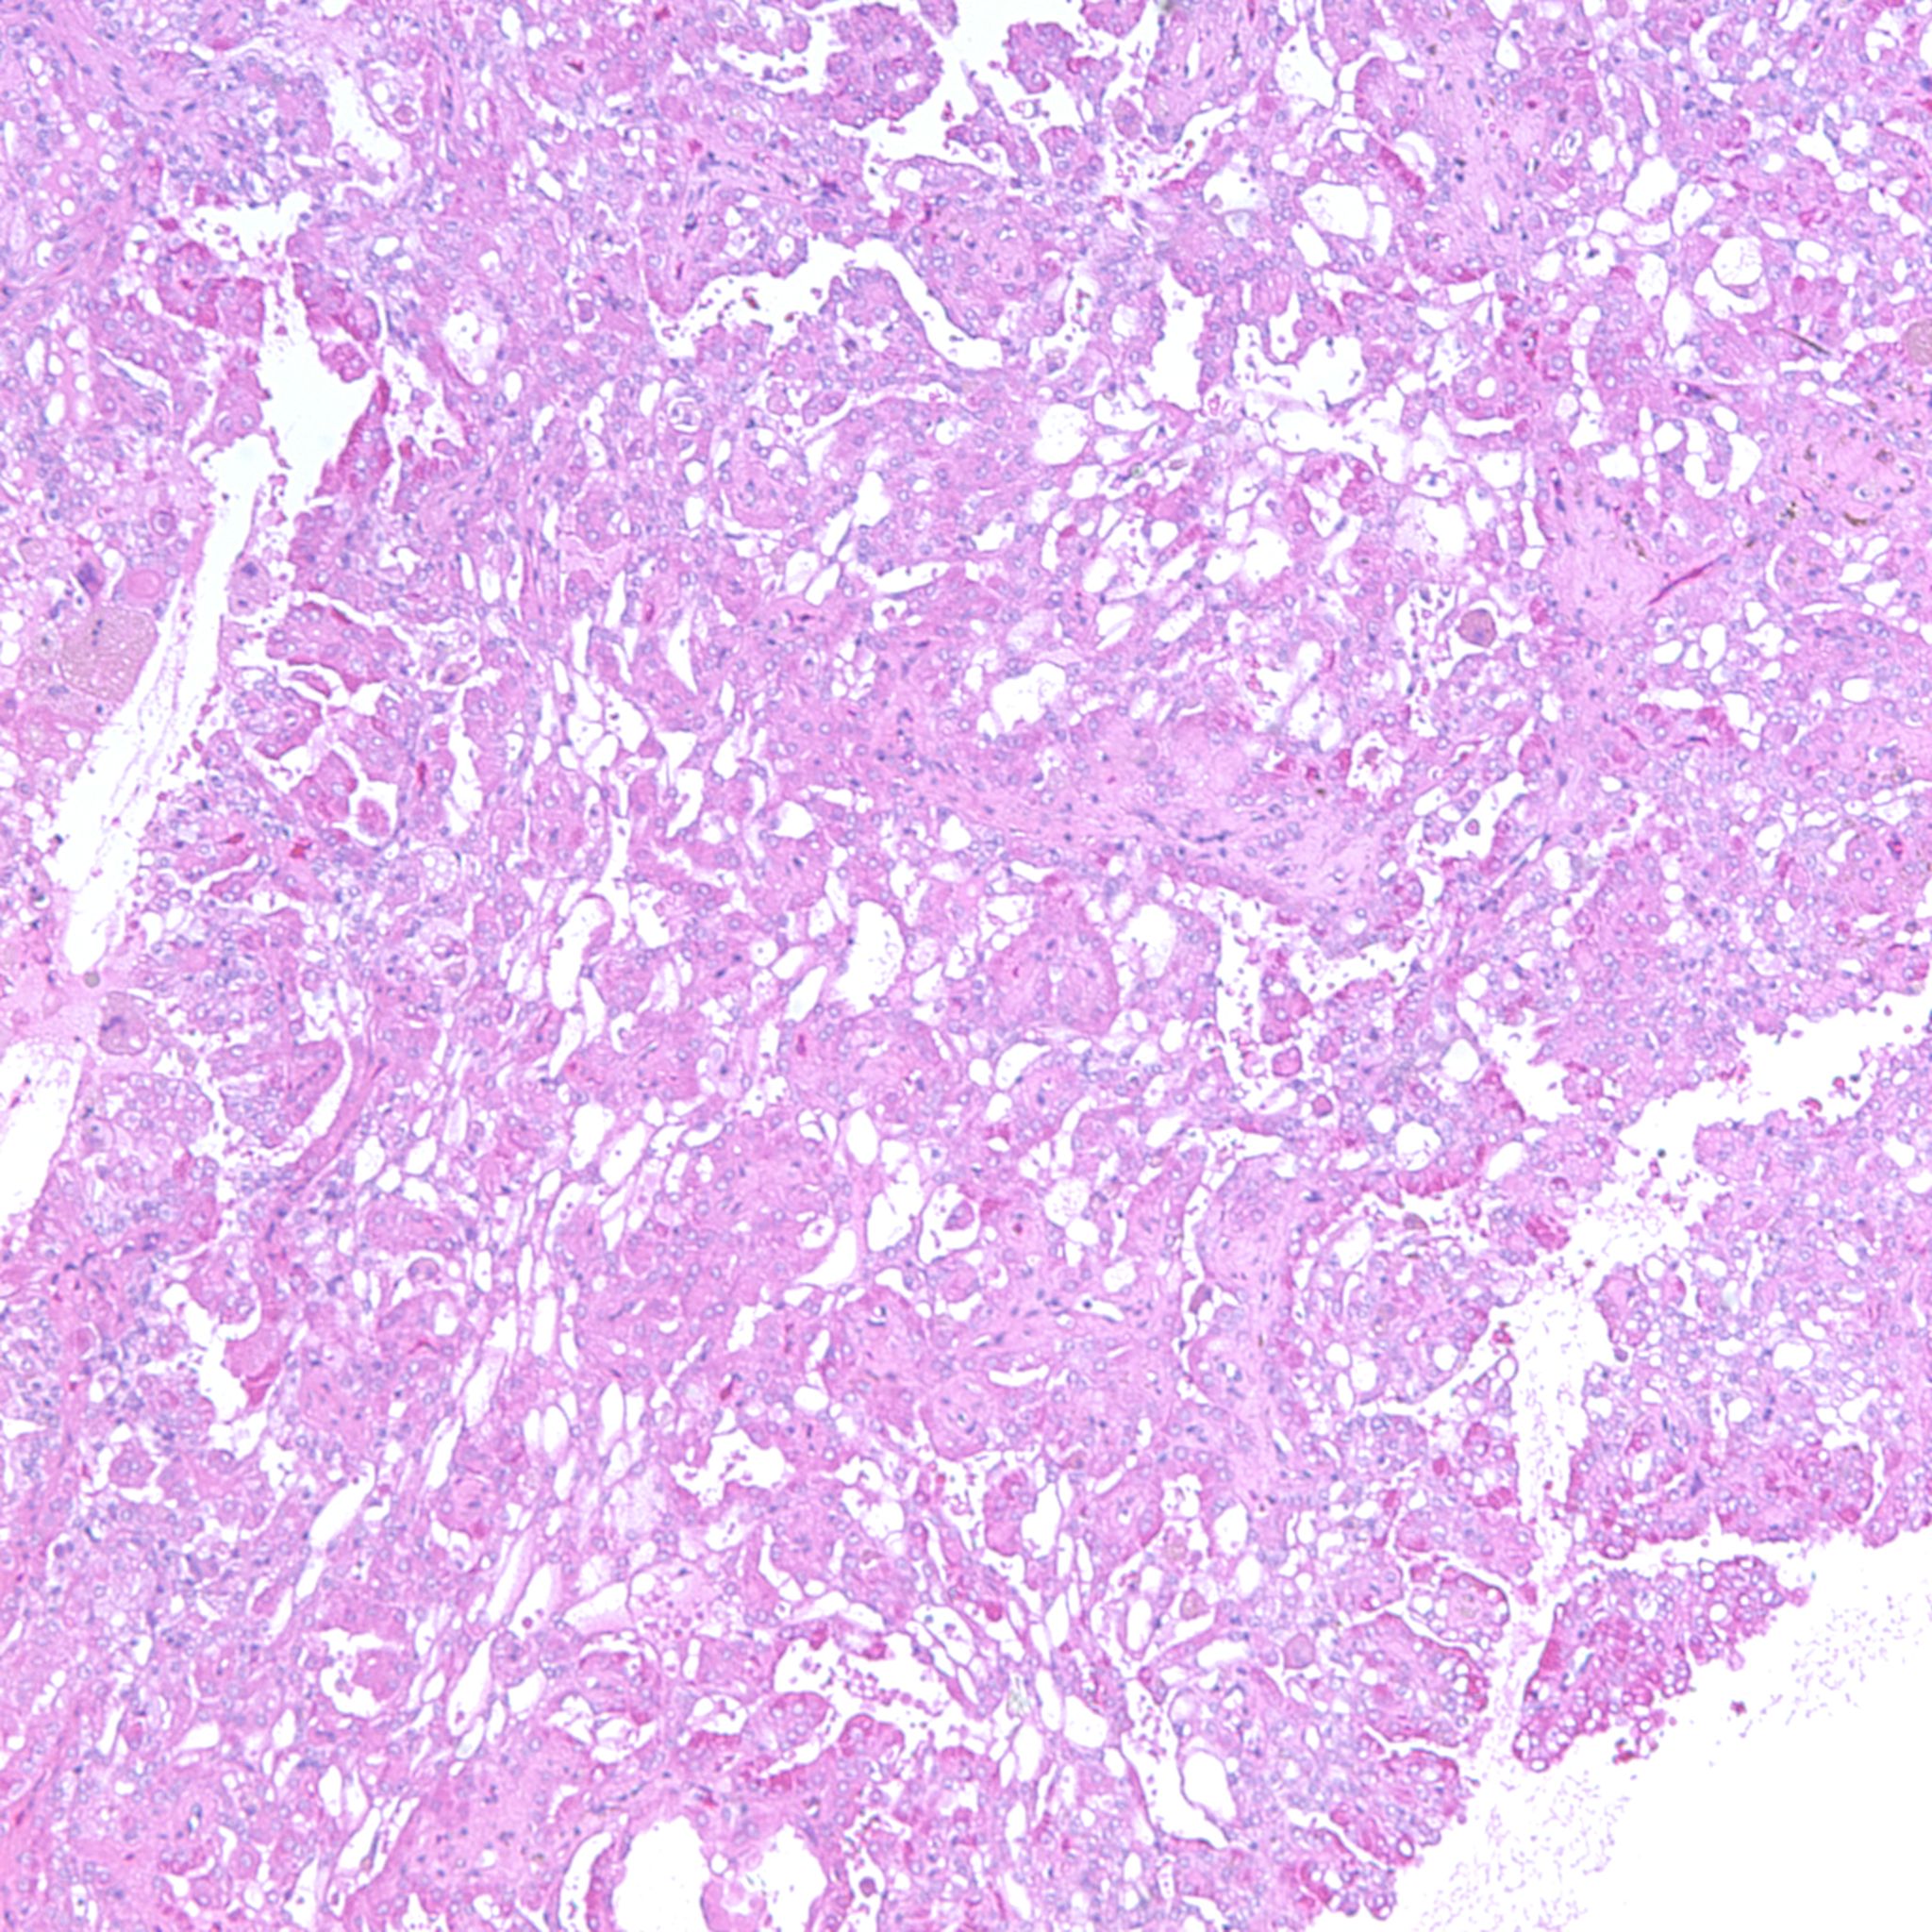

Classification of renal tumors

Case ID: 1237